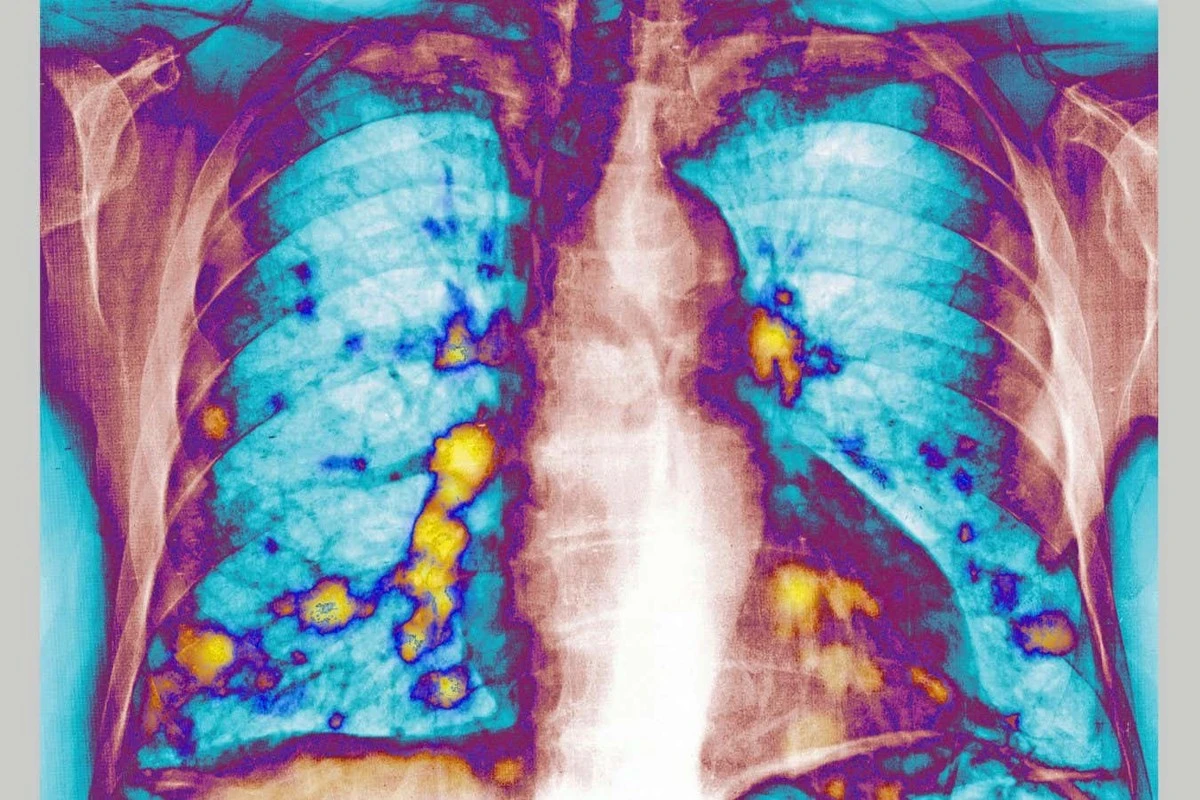

Naukowcy z Imperial College London zauważyli coś niezwykłego podczas badań nad wirusem RSV – tym samym, który co roku powoduje falę zachorowań u dzieci i dorosłych. Okazało się, że myszy zakażone tym wirusem miały o 65–70% mniej guzów przerzutowych w płucach po wprowadzeniu komórek raka piersi.